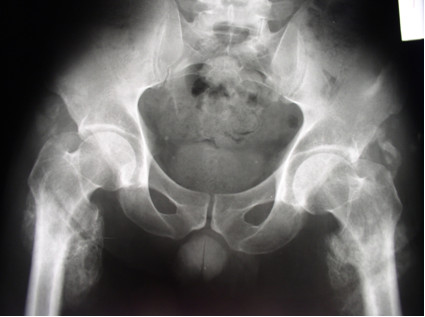

Przedstawiony obraz rtg przedstawia: